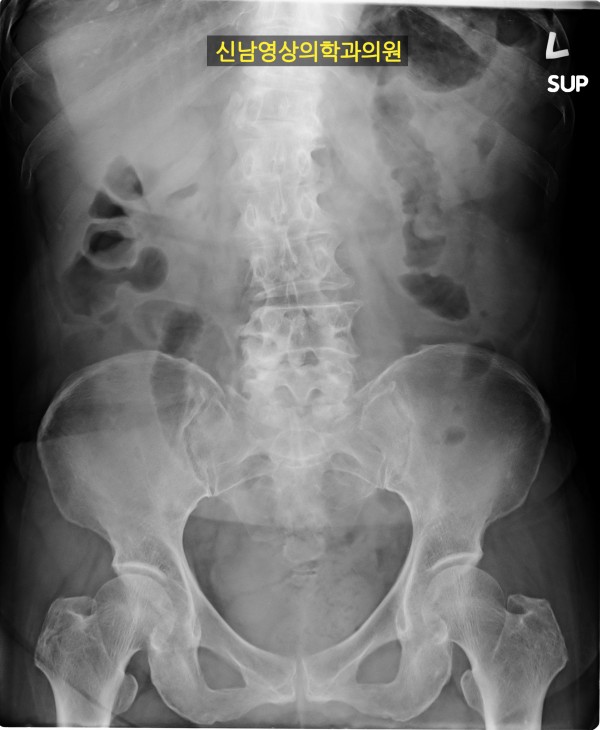

본 환자분께서는 사흘 정도 지속되는 복통과 고열로 내원하신 60대 중반의 환자분입니다.

복통 부위의 병변을 확인하기 위해서 복부 촬영과 복부 초음파검사를 진행했고, 맹장은 이상이 없고, 대장 주위로 복강삼출액(물)이 둘러싸고 있으면서 상행대장부위의 부종이 심하게 발견되었습니다.

원내 피검사상 백혈구 수치가 높아 대학병원 응급실로 전원 조치하고 응급수술을 받으셨고...